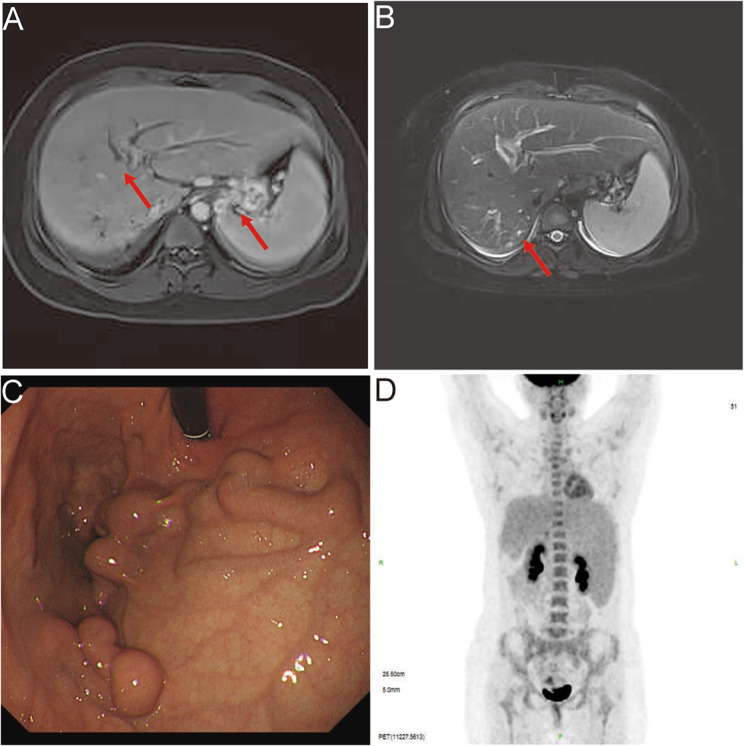

Further, CT (Computed tomography) imaging revealed slight striate shadow in the lower lobes of both lungs, a slight enlargement of the liver’s left lobe, mild dilation of the intrahepatic bile ducts, splenomegaly, esophageal and gastric fundus varices, and numerous tiny cysts in both kidneys. MRI (magnetic resonance imaging) revealed dilated intrahepatic and common bile ducts (Fig. 1 A-B). Upper gastrointestinal endoscopy revealed gastric fundus varices without red signs (Fig. 1 C). Since the patient had elevated serum tumor markers (CA19-9 level>1200 U/ml, ref: <39 U/ml) and CA125 (80.8 U/ml, ref: <39 U/ml), with abnormal levels of ALT and AST, so PET/CT (positron emission tomography/computed tomography) was performed to exclude tumors. PET/CT findings suggested slightly enlarged liver with mild dilatation of the intrahepatic bile ducts, hyperplastic lymph nodes around the portal vein, giant spleen with no increase in FDG (fluorodeoxyglucose) metabolism (Fig. 1 D).

Fig. 1.

Imaging findings of the patient. (A-B) MRI imaging revealed dilated intrahepatic bile duct dilatation, gastric fundic varices, an enlarged spleen and small cyst in the kidney (arrow). (C) Upper gastrointestinal endoscopy revealed gastric fundic varices. (D) PET/CT imaging revealed slightly enlarged liver, hyperplastic lymph nodes around the portal vein, giant spleen with no increase in FDG metabolism and multiple varices in the fundic and retroperitoneum